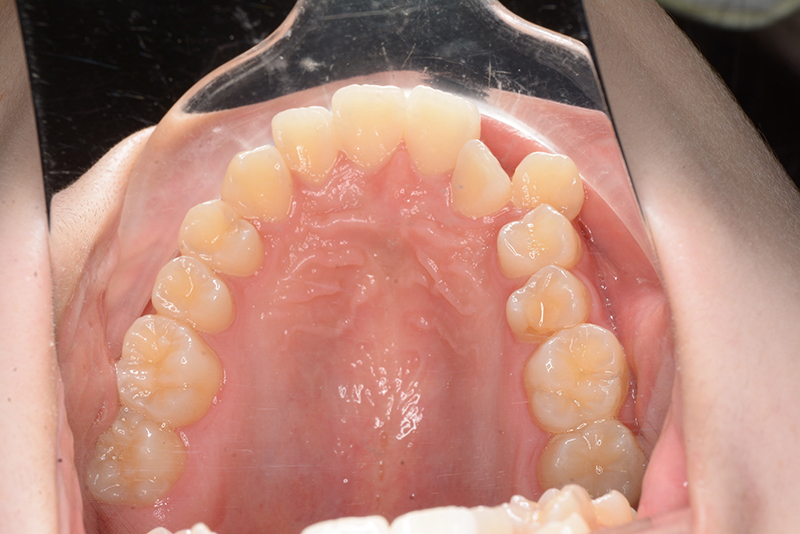

| 口腔内所見 | over jet 3.8mm、over bite 30mm、臼歯関係I級、上下顎前歯部に叢生が認められ、下顎正中は右側へ4.5mm偏位していた。左上5はCRの治療痕が認められた。 |

| 批評・予后 | 治療後において閉唇時の頤筋の過緊張の改善及び咬合の緊密化と歯根のパラレリングが認められ、良好な咬合が確立できたと思う。 現在は保定をしつつ下顎両側第三大臼歯抜歯の抜歯を検討している。 |